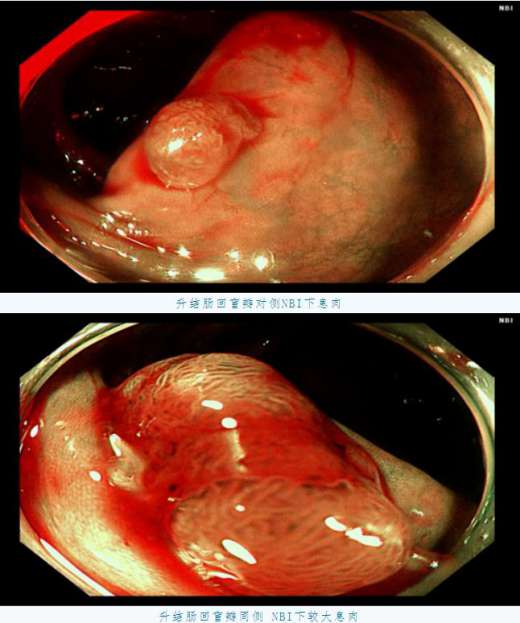

距肛門16cm直腸白光下較大息肉在檢查過(guò)程中我們發(fā)現,C先生在升結腸回盲瓣附近、橫結腸、直腸等部位多發(fā)息肉,個别息肉較大,甚至達到1.5cm以上。且通過(guò)NBI技術進(jìn)行觀察,息肉已經(jīng)有了病變的不良趨勢。

橫結腸白光下息肉,基底部給予亞甲藍生理鹽水黏膜下注射後(hòu)拟行EMR(内鏡下黏膜切除術)術